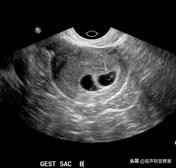

5周+ 、6周+ 声像图

孕7周左右(胚芽11mm 卵黄囊)

胎芽 卵黄囊 心管搏动信号

宫内早孕 (7周左右)